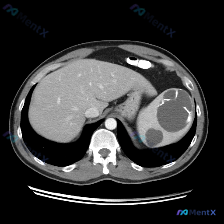

这是一份腹部CT轴位图像:

- 肝脏:实质密度均匀,血管走行正常,未见局灶性占位。

- 脾脏:形态异常,脾实质内见多发、大小不等的囊性病灶,呈圆形/类圆形,边界清晰;最大病灶位于脾中部,囊壁可见明显的环形/弧形高密度钙化(壳状钙化),部分病灶呈低密度流体影。

- 其他:胃、腹主动脉及周围间隙无殊,无腹水,脾门脂肪间隙清晰,无急性渗出。